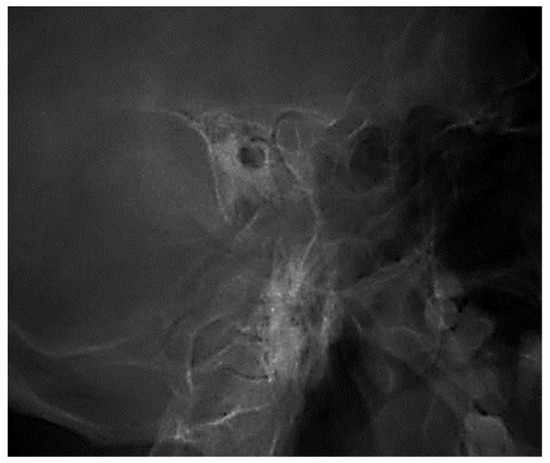

3.1.1. Conventional Radiology

3.1.2. Computed Tomography and Magnetic Resonance Imaging